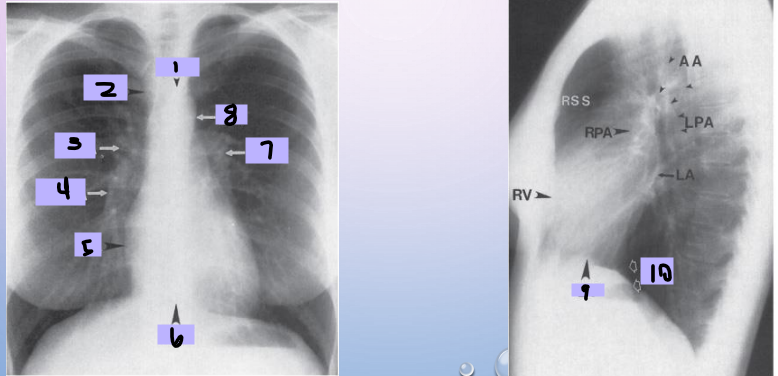

Aortic arch

#1

Superior vena cava

#2

Right pulmonary artery

#3

Right descending pulmonary artery

#4

Right atrium

#5

Right ventricle

#6

Left pulmonary artery

#7

Descending aorta

#8

Left ventricle

#9

Inferior vena cava

#10